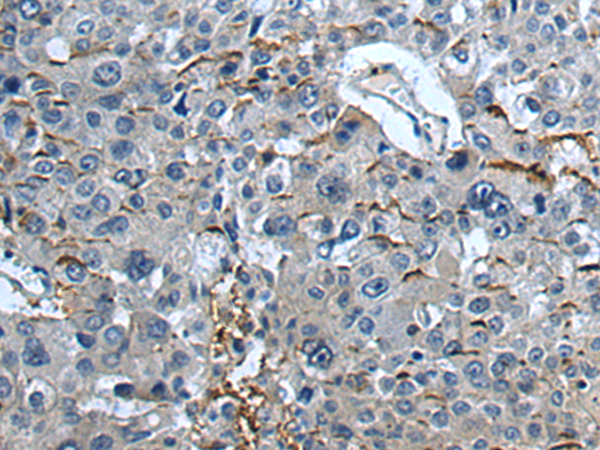

分类: 科研抗体货号: P10760别名: CKLFH; CKLFH1; CKLFSF1应用: IHC反应种属: Human